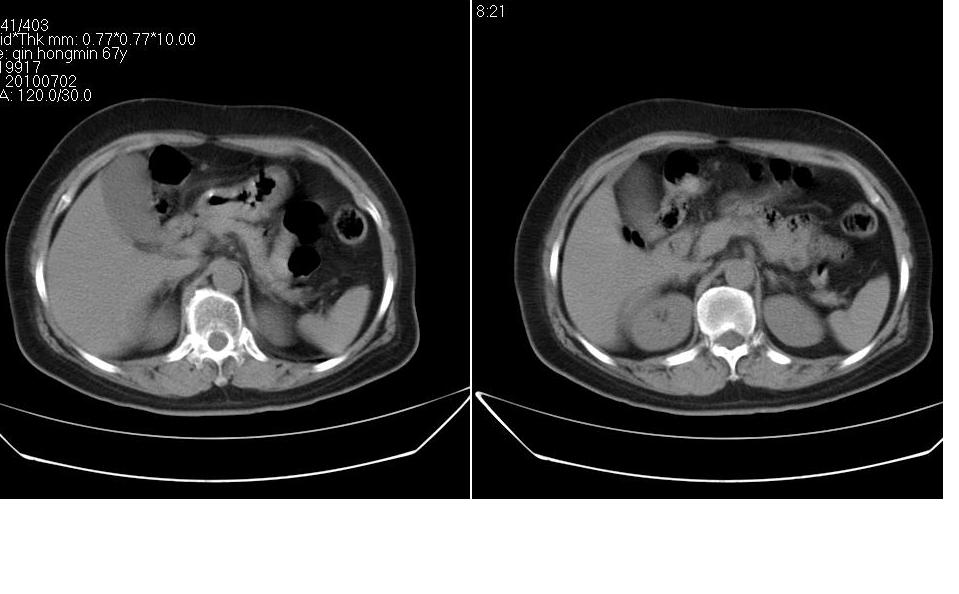

女 67岁,以腹疼就诊,不发热,八年前有肠梗阻病史,炎热的夏天,下午又吃了两块西瓜及两个桃子,以后无大便,不放屁。

右侧腹部膨隆左侧塌陷,小肠积气积液扩张,肠袢迂曲扭转,远侧肠曲无异常,考虑高位肠梗阻,小肠扭转可能,具体可能为3、4组,建议扫描全腹。此外胆囊大。先对症保守治疗,必要时手术。

腹内疝很罕见的,此处可发生盲肠旁疝但不符。那个是粪石??